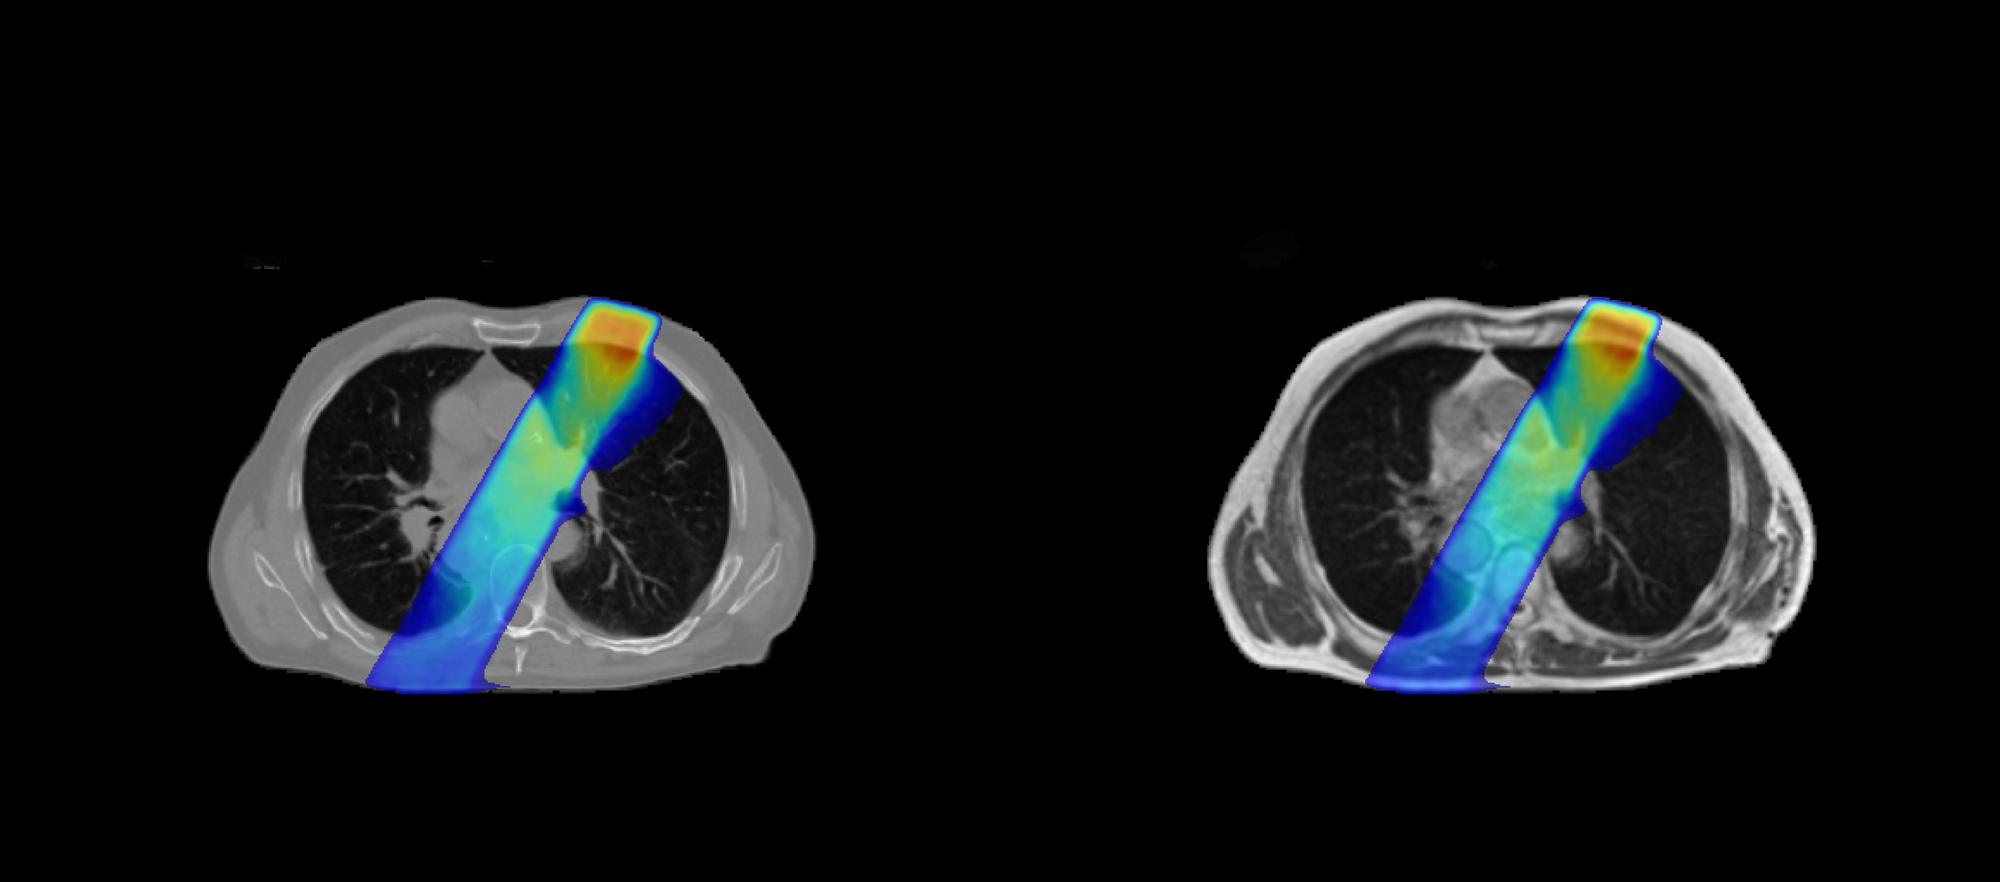

DoseRAD2026 aims to benchmark state-of-the-art methods for fast and accurate radiation dose calculation, for both photon and proton radiotherapy, using either computed tomography (CT) or MRI as input.

The challenge consists of four tasks reflecting current and emerging radiotherapy technologies:

-

Photon dose calculation on CT

Relevant for intensity-modulated photon therapy using volumetric modulated arc therapy (VMAT), the standard treatment modality for the majority of patients. -

Photon dose calculation on MRI

Supporting MRI-guided radiotherapy systems (MRI-linacs), which enable online adaptive treatment based on high soft-tissue contrast imaging.